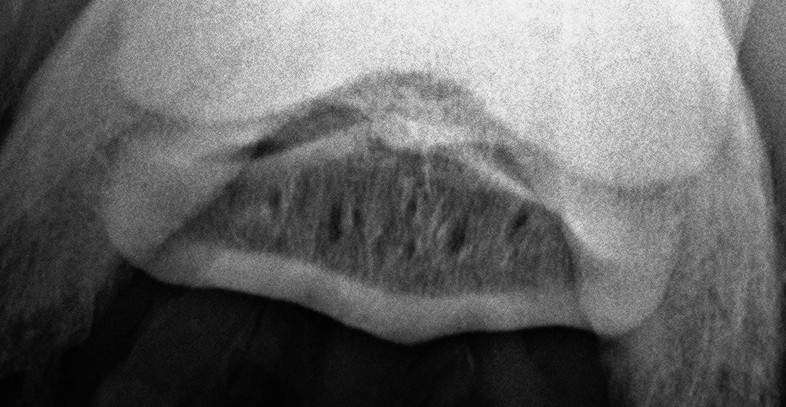

A nyírcsonti burza beinjekciózása.

A szúrás helyességét röntgennel ellenőrizzük.